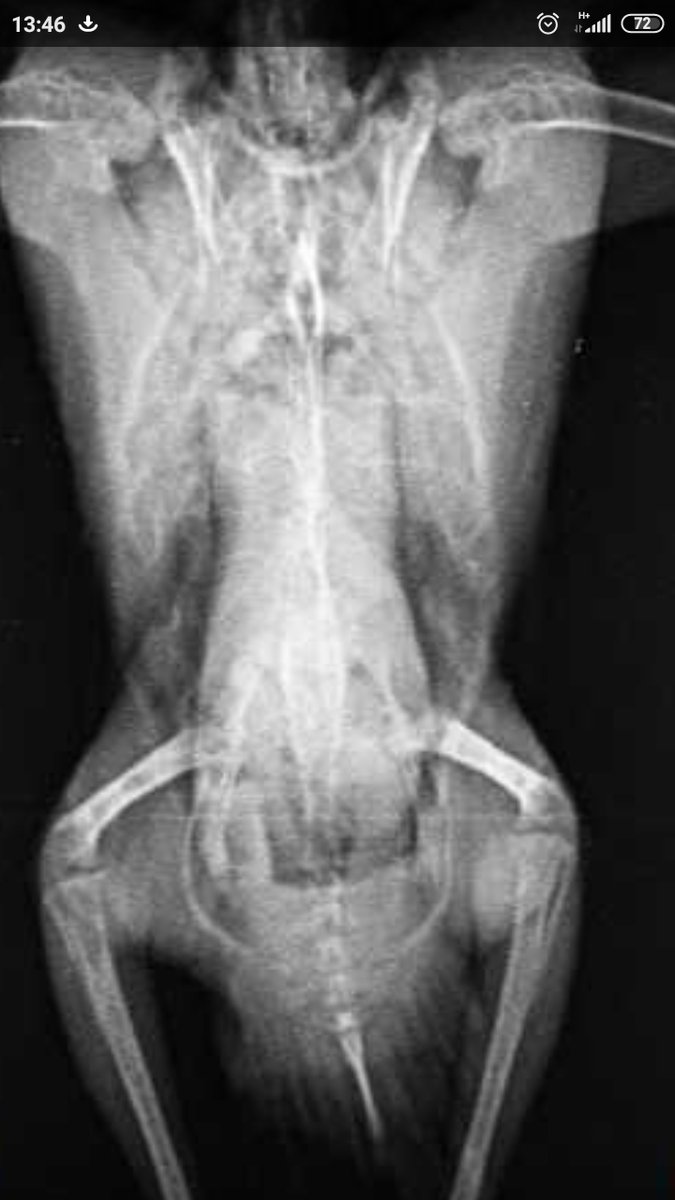

Здравствуйте. Возможно ли определить пол по снимку рентгена? 2 птицы, одна точно самка, вторая вроде тоже, но у меня кладку не делала. Поведение самца с маской (что не размножалась у меня, подло заставляет думать, что это самец подавленный поведением моего самца. Сдать гормоны нет возможности. На одном из снимков есть 100% самка (дала у меня 3 выводка) Кореллы взрослые, старше 1.5 лет О том что по рентгену есть проблемы со здоровьем, я в курсе, для назначений снимки и сделаны, лечение назначено, контроль через месяц, но лечение помогает. Снимкам примерно 3 недели.